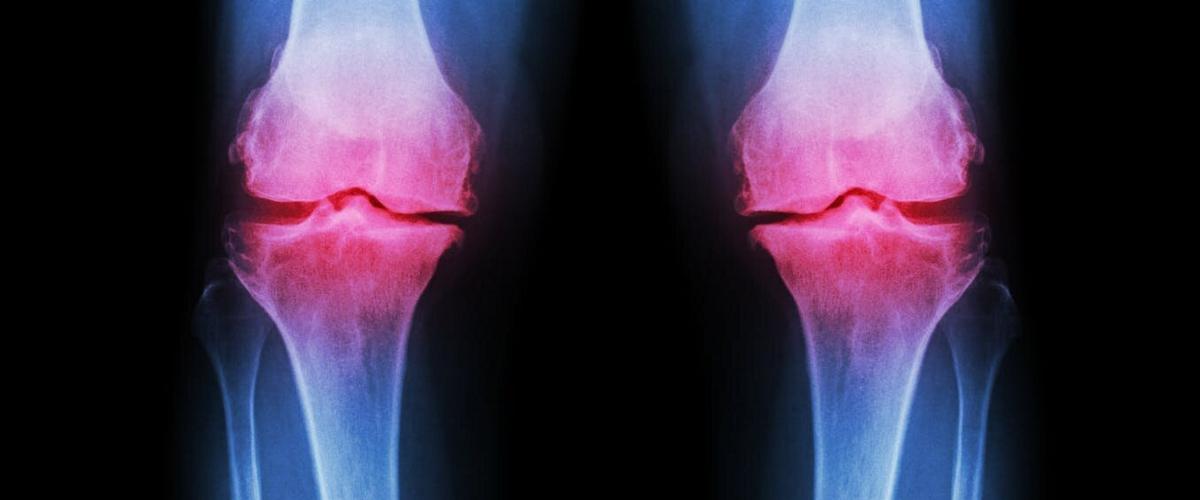

Исследователи из Университета штата Орегон впервые представили полный анализ клеточных процессов, которые характерны для пораженных остеоартрозом суставов. Работа, о которой рассказывает Science Daily, позволит лучше понять, как лекарства, физические упражнения и диета влияют на развитие этой болезни.

В настоящее время от остеоартроза страдает около 50 млн американцев, а к 2040 году эта цифра возрастет до 78 млн. На этом фоне исследование механизмов развития этой болезни выглядит особенно актуальным. Помимо прочего, новая методика может пролить свет на самые ранние этапы возникновения остеоартроза, что облегчит его диагностику и позволит лечить болезнь эффективнее.